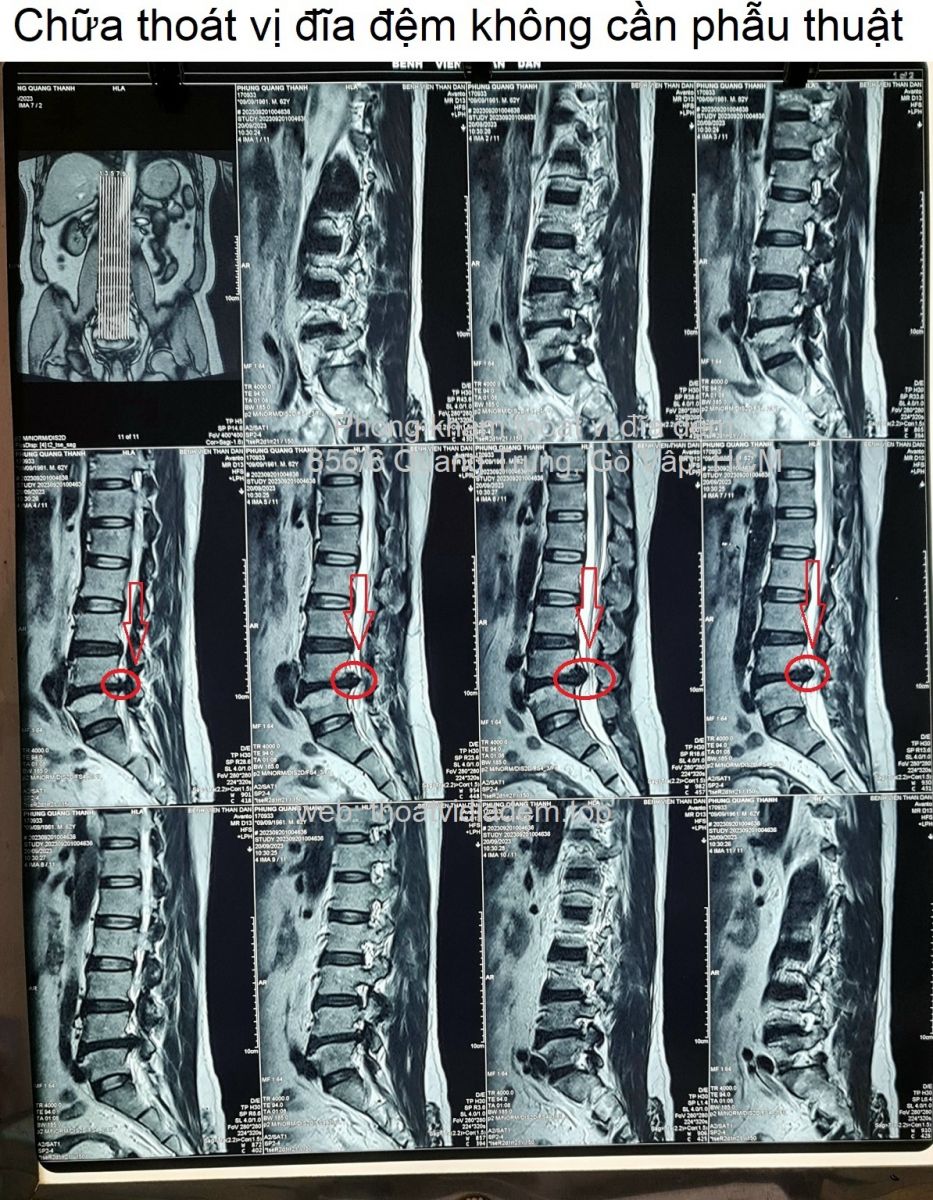

Chữa thoát vị đĩa đệm không cần phẫu thuật

Chữa thoát vị đĩa đệm không cần phẫu thuật, không nằm viện. Đây là cách chữa của thầy thuốc đông y Nguyễn Văn Minh ở phòng khám đông y Bảo Minh. Lương y Nguyễn Văn Minh có kinh nghiệm trên 25 năm trong nghề; khám bệnh, bắt mạch, kê đơn thuốc điều trị thoát vị đĩa đệm.

Thoát vị đĩa đệm L4-L5, L5-S1, chèn ép rễ thần kinh Thoát vị đĩa đệm L4-L5 ra sau #5mm, chèn ép bao màng cứng, gây hẹp lỗ liên hợp hai bên, chèn ép rễ thần kinh L4, L5. Thoát vị đĩa đệm L5-S1 trung tâm ra sau #5mm, chèn ép mặt trước bao màng cứng, gây hẹp lỗ liên hợp hai bên, chèn ép rễ thần kinh L5, S1.❮ đọc tiếp ❯

Chữa thoát vị đĩa đệm chèn ép rễ thần kinh cho chú Hùng ở Bình Dương.Lương y Nguyễn Văn Minh - Phòng khám Đông y Bảo Minh chỉ chia sẻ ý kiến và kết quả MRI khi được sự đồng ý từ quý khách, sau này quý khách nào không muốn xuất hiện ở đây nữa, chúng tôi sẽ gỡ bài đăng xuống. Xin trân trọng cảm ơn quý khách đã tin tưởng vào uy tín của phòng khám.❮ đọc tiếp ❯